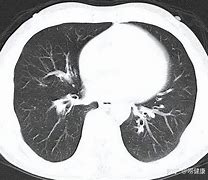

癌症,这个令人闻风丧胆的疾病,一直以来都是医学研究的重要领域。当癌症患者不幸去世,人们往往会对患者体内的癌细胞的命运产生好奇:这些曾经疯狂增殖的细胞,在宿主生命终结后,是否也会随之死亡?本文将深入探讨这一问题,解析癌细胞在宿主去世后的生命周期及其背后的生物学机制。

在探讨癌细胞的最终命运之前,我们首先需要了解癌细胞的基本特性。癌细胞与正常细胞最大的不同在于其无限增殖的能力、对生长信号的依赖性丧失、对细胞死亡信号的抵抗以及侵袭和转移的能力。这些特性使得癌细胞能够在宿主体内不受控制地生长,最终导致宿主生命的威胁。

当癌症患者去世时,其体内的生理环境会发生急剧变化。血液循环停止,氧气和其他营养物质的供应中断,体内的酸碱平衡和温度调节也会失效。这些变化对癌细胞来说是致命的。癌细胞虽然具有一定的生存优势,但它们仍然依赖于宿主体内的稳定环境来维持其生存和增殖。